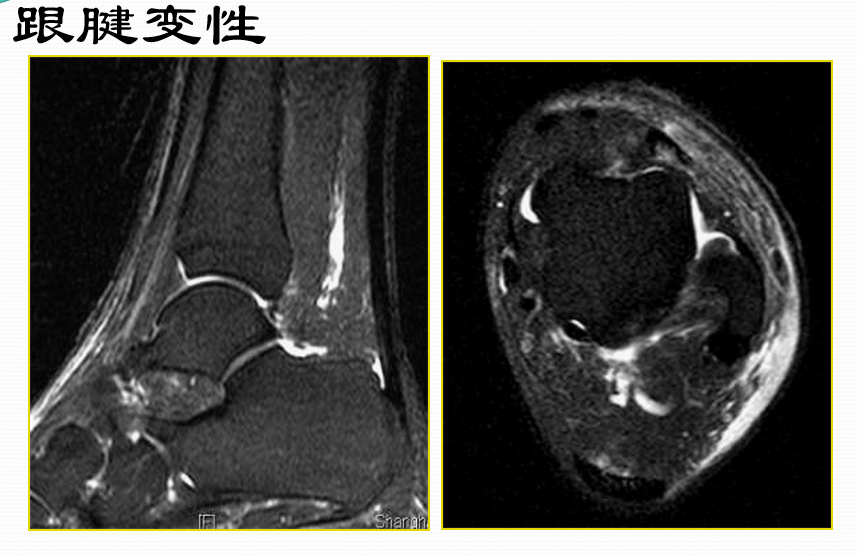

跟腱断裂

MR表现:(信号+形态)

• 正常跟腱呈均匀低信号

• 脂肪抑制T2WI图像上,跟腱内部或跟腱周围软组织出血或水肿表现为信号增高,跟腱断裂/撕裂表现为跟腱连续性中断或波浪状回缩

• 跟腱近端回缩,跟腱边缘磨损,呈螺旋状形态

• 撕裂处增粗的近端与远端之间可见疏松的连接